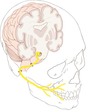

Which 3 pairs of muscles are responsible for closing the jaw?

Masseter, Temporalis and Medial pterygiod

Which pair of muscles is responsible for opening the jaw?

Lateral pterygoid

What is the origin and insertion of the masseter m.?

Angle of mandible to zygomatic arch

What is the origin and insertion of the temporalis m.?

Coronoid process of mandible to temporal fossa

What is the origin and insertion of the medial pterygoid m.?

Angle of mandible (medial side) to pterygoid plates of sphenoid bone

What is the origin and insertion of the lateral pterygoid m.?

Condyle of mandible to pterygoid plates of sphenoid bone

Which nerve supplies all of the muscles acting on the jaw?

Mandibular division of trigeminal nerve – CN V3

What is the intracranial course of the trigeminal nerve?

Leaves the pons, and passes inferior to the edge go the tentorium cerebella between the posterior and middle cranial fosse

How does V2 - maxillary branch of trigeminal leave the skull?

Through the sphenoid bona via the foramen rotundum